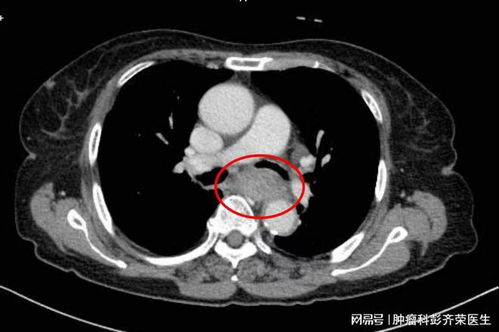

复旦大学的研究团队采用了一系列先进的生物信息学分析和实验技术,包括基因组学、转录组学和蛋白质组学等,对食管鳞癌患者的肿瘤组织样本进行了深入分析。通过大规模的数据挖掘和生物标志物筛选,研究团队发现了一个新的分子标志物——一种特定的蛋白质表达水平与食管鳞癌患者的预后密切相关。

进一步的实验验证表明,该蛋白质不仅能够作为食管鳞癌的独立预后生物标志物,而且其表达水平的改变还与肿瘤的侵袭性和转移能力有关。更为重要的是,研究团队发现通过调节该蛋白质的活性,可以有效抑制食管鳞癌细胞的生长和扩散,提示其可能成为食管鳞癌治疗的新靶点。